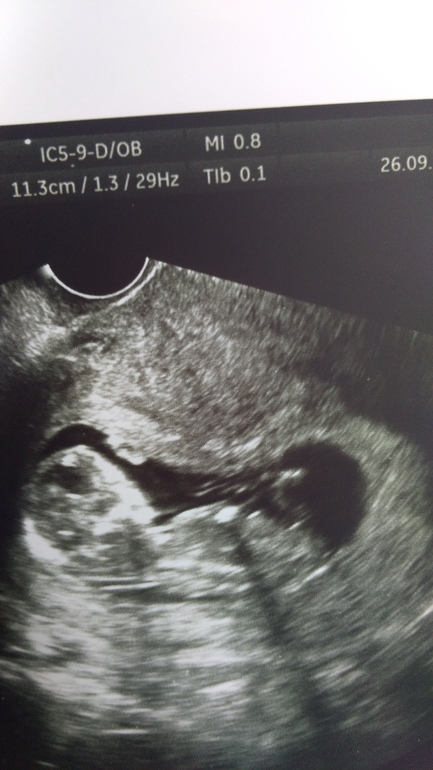

Пол малыша

Пол малышаДевочки,как вы там смотрите по бугорку?или его нет на фото?Я не понимаю ничего,но интересно,узист сказал не уверен,не стал говорить.

Фото под кат

Вот и у меня по задней и сказал неудачно совсем лежит,как не вертел.

Говорит бывает,что прям сразу видно,а у вас что-то среднее)))